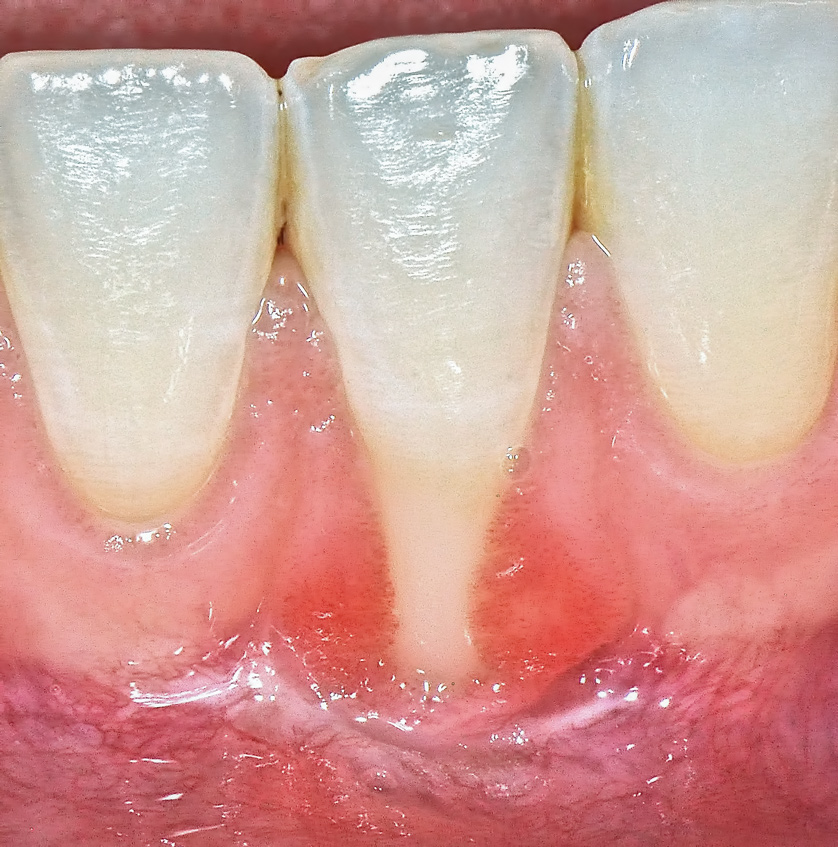

The workshop's group on periodontal soft-tissue root coverage procedures evaluated the predictability of root coverage procedures for single- and multiple-tooth Miller Class I and II10 periodontal recession defects. The workshop concluded that predictable root coverage was possible for Miller Class I and II recession involving a single tooth. When compared with the use of acellular dermal matrix graft (ADMG) (donor tissue) or EMD (porcine origin), procedures using a subepithelial connective tissue graft (SCTG) harvested from the patient's palate provided the best root coverage outcomes in conjunction with a coronally advanced flap.11 As alternatives to autogenous donor tissue, the workshop found strong evidence to support the use of an ADMG or EMD in conjunction with a coronally advanced flap and limited evidence to support the use of platelet-derived growth factor and xenogeneic collagen matrix.11 In addition, root coverage procedures were found to be effective for Miller Class I and II recession defects affecting multiple teeth, although the evidence is limited.11 Figure 1 and Figure 2 show the pretreatment and 1-year postoperative views of a soft-tissue root coverage treatment with SCTG and EMD that used a coronally advanced flap and a tunneling procedure. Figure 3 and Figure 4 depict the pretreatment and 3-year postoperative views of a root coverage procedure with ADMG and EMD that used a coronally advanced flap and a tunneling procedure (this patient was noncompliant following surgery and did not return to the office until the 3-year postoperative appointment).

(1.) Pretreatment view of single incisor with gingival recession exposing the root.

Figure 1

(2.) Postoperative view after one year following treatment with SCTG (harvested from palate) and EMD using a coronally advanced flap and a tunneling procedure.

Figure 2